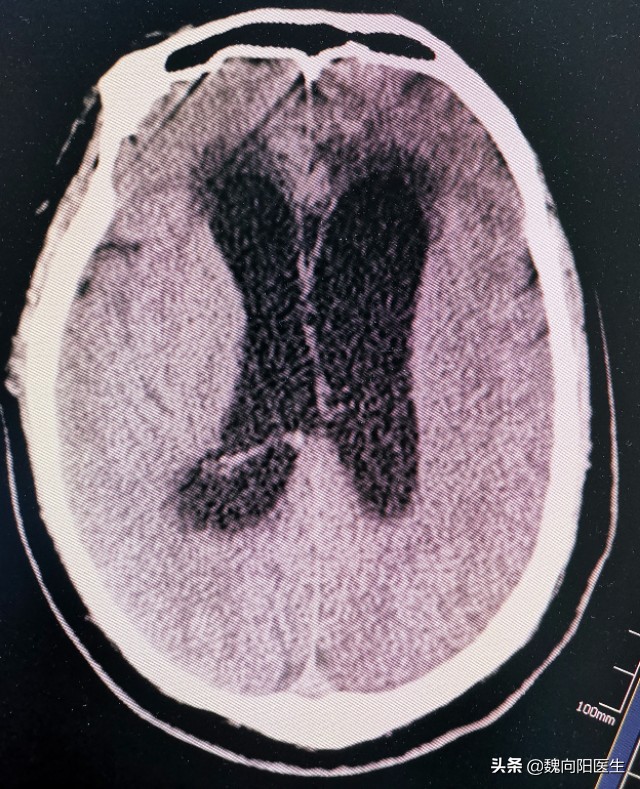

其实,脑内增加的并不是“水”,是脑积液。脑积液是由脑室内脉络丛分泌的一种正常的生理液,每天分泌400~500毫升。但是在正常生理状态下,通过脑膜颗粒又重新回收,形成一个动态的平衡。

蛛网膜下腔出血后,在蛛网膜下腔中充满了血液。尤其是出血量较大时,凝血块可以阻塞脑室与外部的通道,而且陈旧的血液封闭了脑脊液吸收结构——蛛网膜颗粒。导致脑室内不断生成的脑脊液有流不出来,甚至蛛网膜颗粒回收减少或不能回收,于是造成脑室“水增加”,引起脑室扩大,这就是脑积水。

- 蛛网膜下腔出血急性期的脑积水有时是很严重的,连同出血和脑水肿一起引起明显的颅内压升高,因而可危及病人的生命。